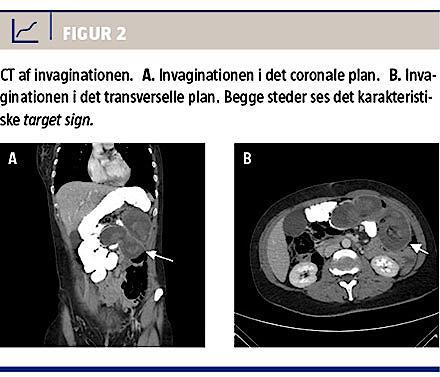

I september 2012 fik hun om natten pludseligt indsættende, svære, abdominale smerter med udstråling til ryggen og blev akut indlagt på en afdeling med regionsfunktion for fedmeoperationer. Der blev foretaget akut CT på mistanke om intern herniering, hvilket sammen med mistanke om invagination i jejuno-jejunum-anastomosen og dilaterede tyndtarme distalt herfor blev bekræftet (Figur 2). Seks timer efter smertedebut blev der foretaget diagnostisk laparoskopi, men der blev konverteret til åben operation pga. manglende overblik. Der blev fundet invagination af fællesbenet op i både fødebenet og galdebenet af anastomosen. Invaginatet blev forsigtigt reponeret med vital tarm. Der blev foretaget peroperativ gastroskopi til 40 cm distalt for jejuno-jejunum-anastomosen, og man fandt ingen forklaring på invaginationen. Der var ikke tegn til intern herniering, og der blev anlagt en gastrostomisonde i den udshuntede ventrikel til aflastning. I invaginatets omslagsfold fandt man 20 cm påvirket tarm, som umiddelbart fremstod vitalt, men det blev besluttet at foretage en second look-operation efter et døgn. Her fandt man fortsat påvirkning af tarmstykket, som man valgte at recesere med primær anastomose. Histologisk blev der fundet iskæmisk nekrose.